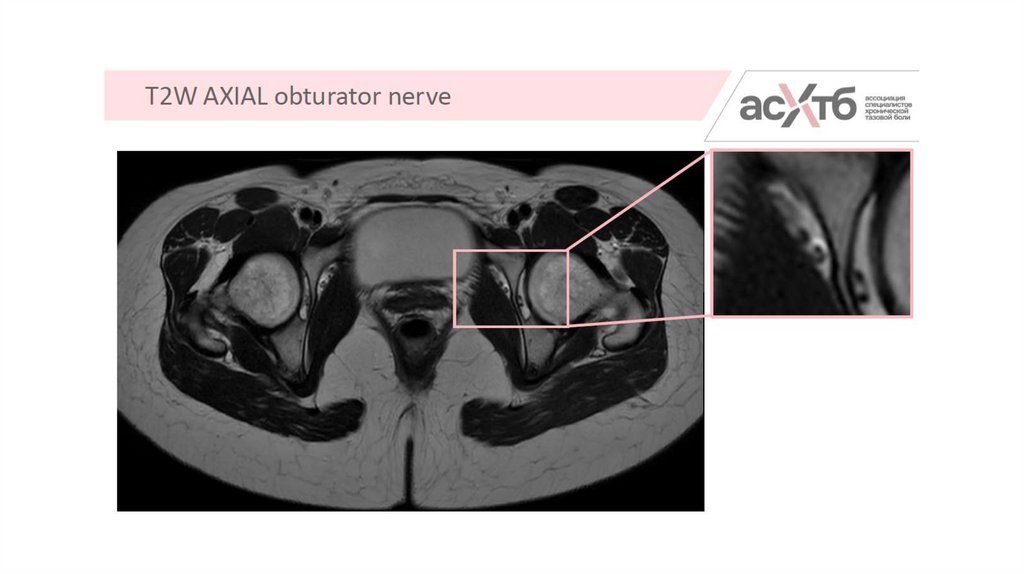

5.

7. МР-нейрография

8. Режимы